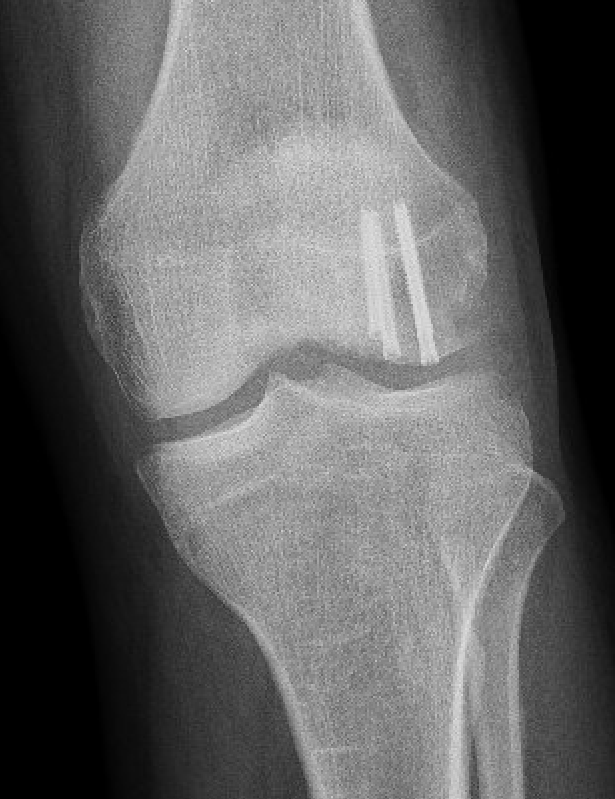

Xray

Look for osteochondral fractures

- skyline xray: suprapatella pouch

- lateral xray: notch

- AP xray: gutters

Osteochondral fracture visible on skyline view

Loose body in notch with donor site from patella

Loose body in lateral gutter

Large medial patella osteochondral fracture

Large lateral femoral condyle osteochondral fracture